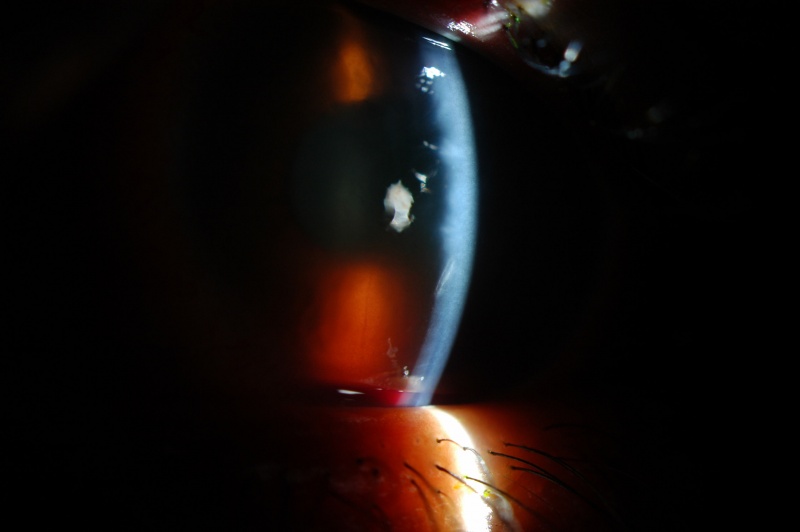

Slit-beam photo with hyphema visible within the inferior anterior chamber. (Same eye as the picture above)

| current | 12:43, September 1, 2011 | 3,008 × 2,000 (195 KB) | Gregory.W.Oldham (talk | contribs) | Slit-beam photo with hyphema visible within the inferior anterior chamber. (Same eye as the picture above) |